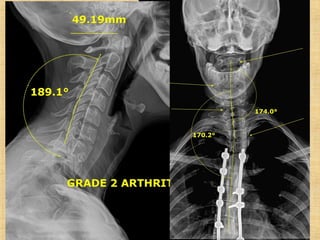

Are Missing lateral Lordotic Curves…“Linda”

13 neck surgeries = is a C1 Technique

Scoliosis Patients Are Missinglateral Lordotic Curves…“Linda”

13 neck surgeries= is a C1 Technique important?